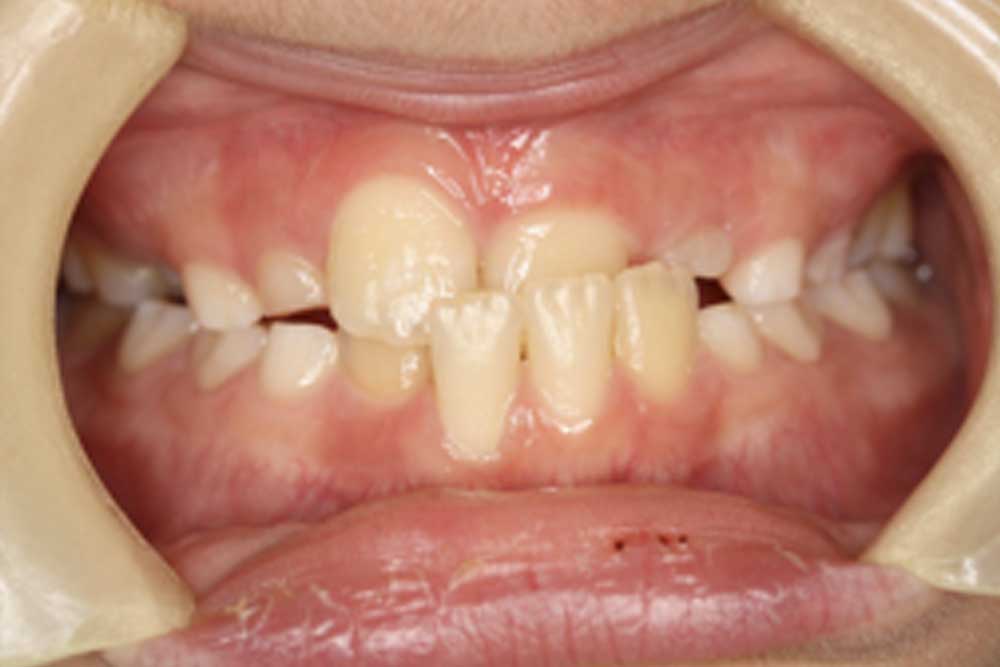

①子どもの受け口の矯正治療例(8歳男児・治療期間6ヶ月)

年齢・性別 8歳男児

治療期間 6ヶ月

抜歯 なし

治療費 44万円(税込)

備考 自閉症

小学生の男児です。前歯の咬み合わせが逆になってしまっていることを親御さんが気にされて来院されました。このままでは成人になった時に、手術をしなければ良好な咬み合わせが得られない可能性が非常に高い状況です。

分析の結果、取り外しの出来る矯正装置を使用することで改善を図りました。患者さんは軽度の自閉症を患っており、治療当初コミュニケーションが難しい時期もありました。しかし粘り強く対話していくことで次第に打ち解けられ、矯正装置を大変真面目に使用して頂くことが出来ました。結果的に前歯の咬み合わせは改善しました。これで手術の可能性は限りなく0%になりました。